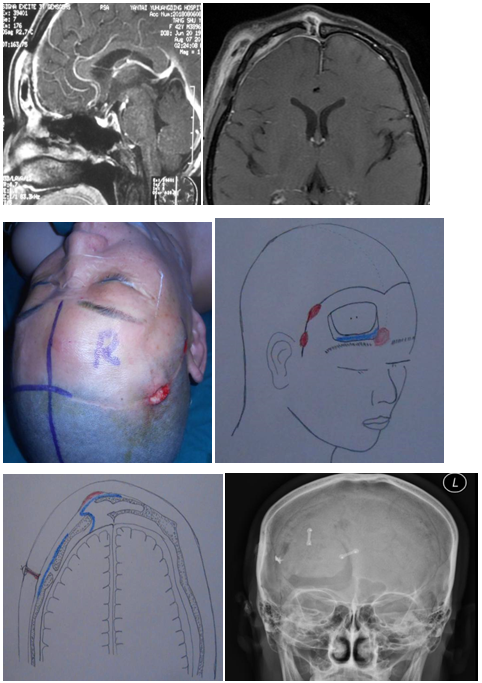

病人女42岁鞍结节脑膜瘤术后2年,眶周红肿2月,刀口不愈合,有两处破溃,流脓,额中部隆起,当地换药后不见效。

拆线前刀口愈合良好,定时拆线

手术情况:原切口开颅,额窦内清除骨蜡,内镜扩大额隐窝,碘仿纱条及引流管引流术腔至鼻腔,一周后拔出纱条,病人出院。

神经外科开颅术后刀口不愈合,必有原因,一是附近有副鼻窦或乳突腔,副鼻窦内常有骨蜡,导致额窦腔引流不畅,轻者额中部无痛性隆起,严重者可在薄弱处破溃。二是过多人工材料的使用,引流不畅时细菌在人工材料上定置,导致感染的发生。